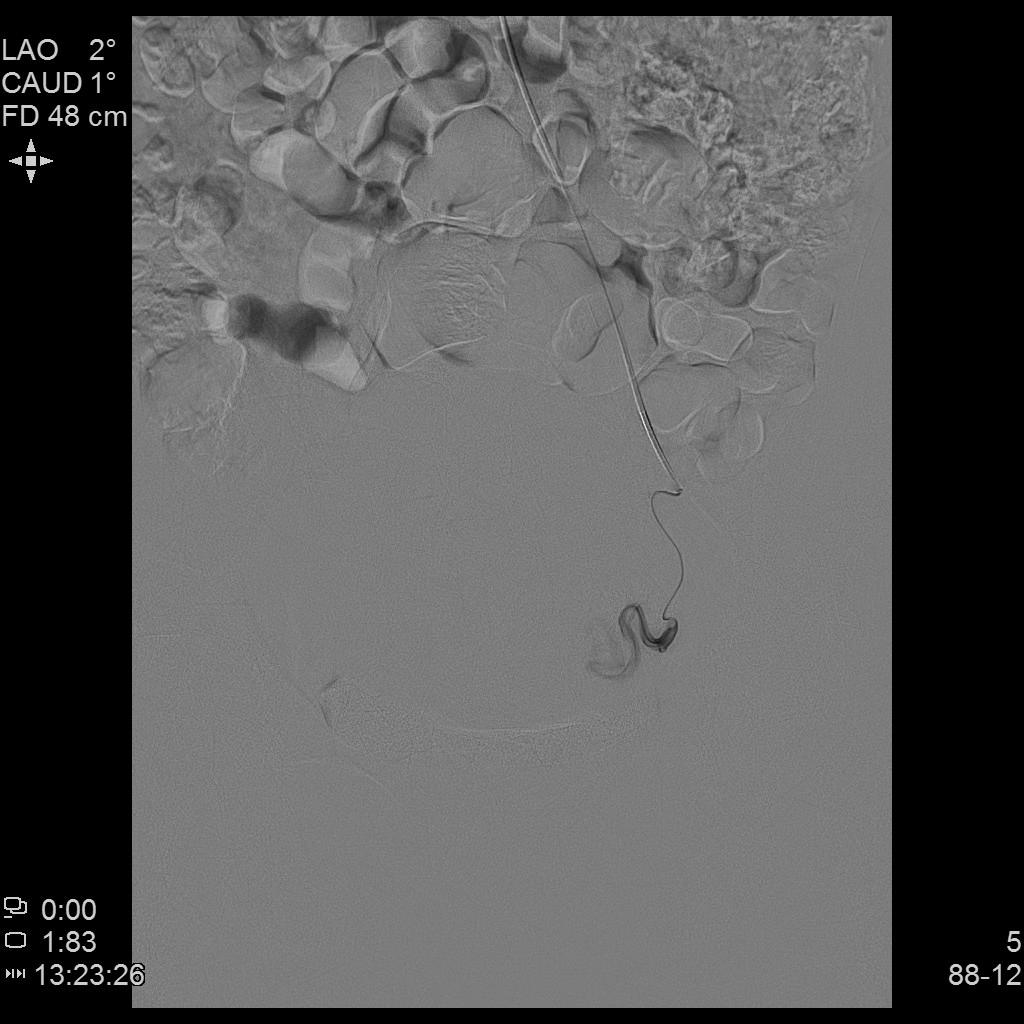

右侧子宫动脉造影

左侧子宫动脉造影

左侧子宫造影